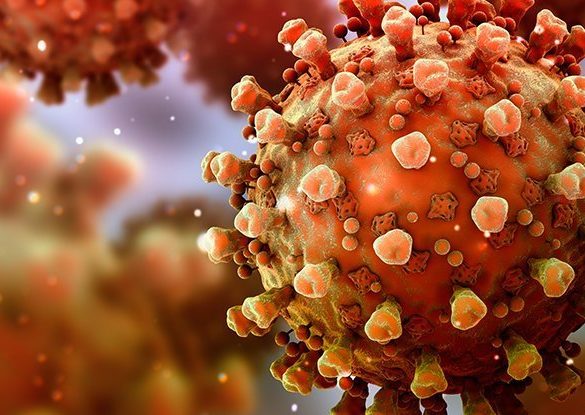

Scientists in California are increasingly worried about the state’s “homegrown” coronavirus variant, with studies now showing that the variant is...

The fast-spreading “UK variant” of the coronavirus could become the predominant strain in the United States by March, according to...